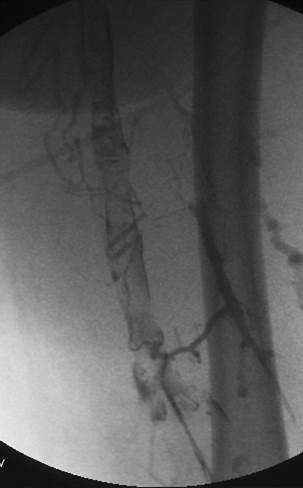

Venograma de la pierna izquierda donde se muestra un trombo oclusivo en las venas profundas más visualizadas.